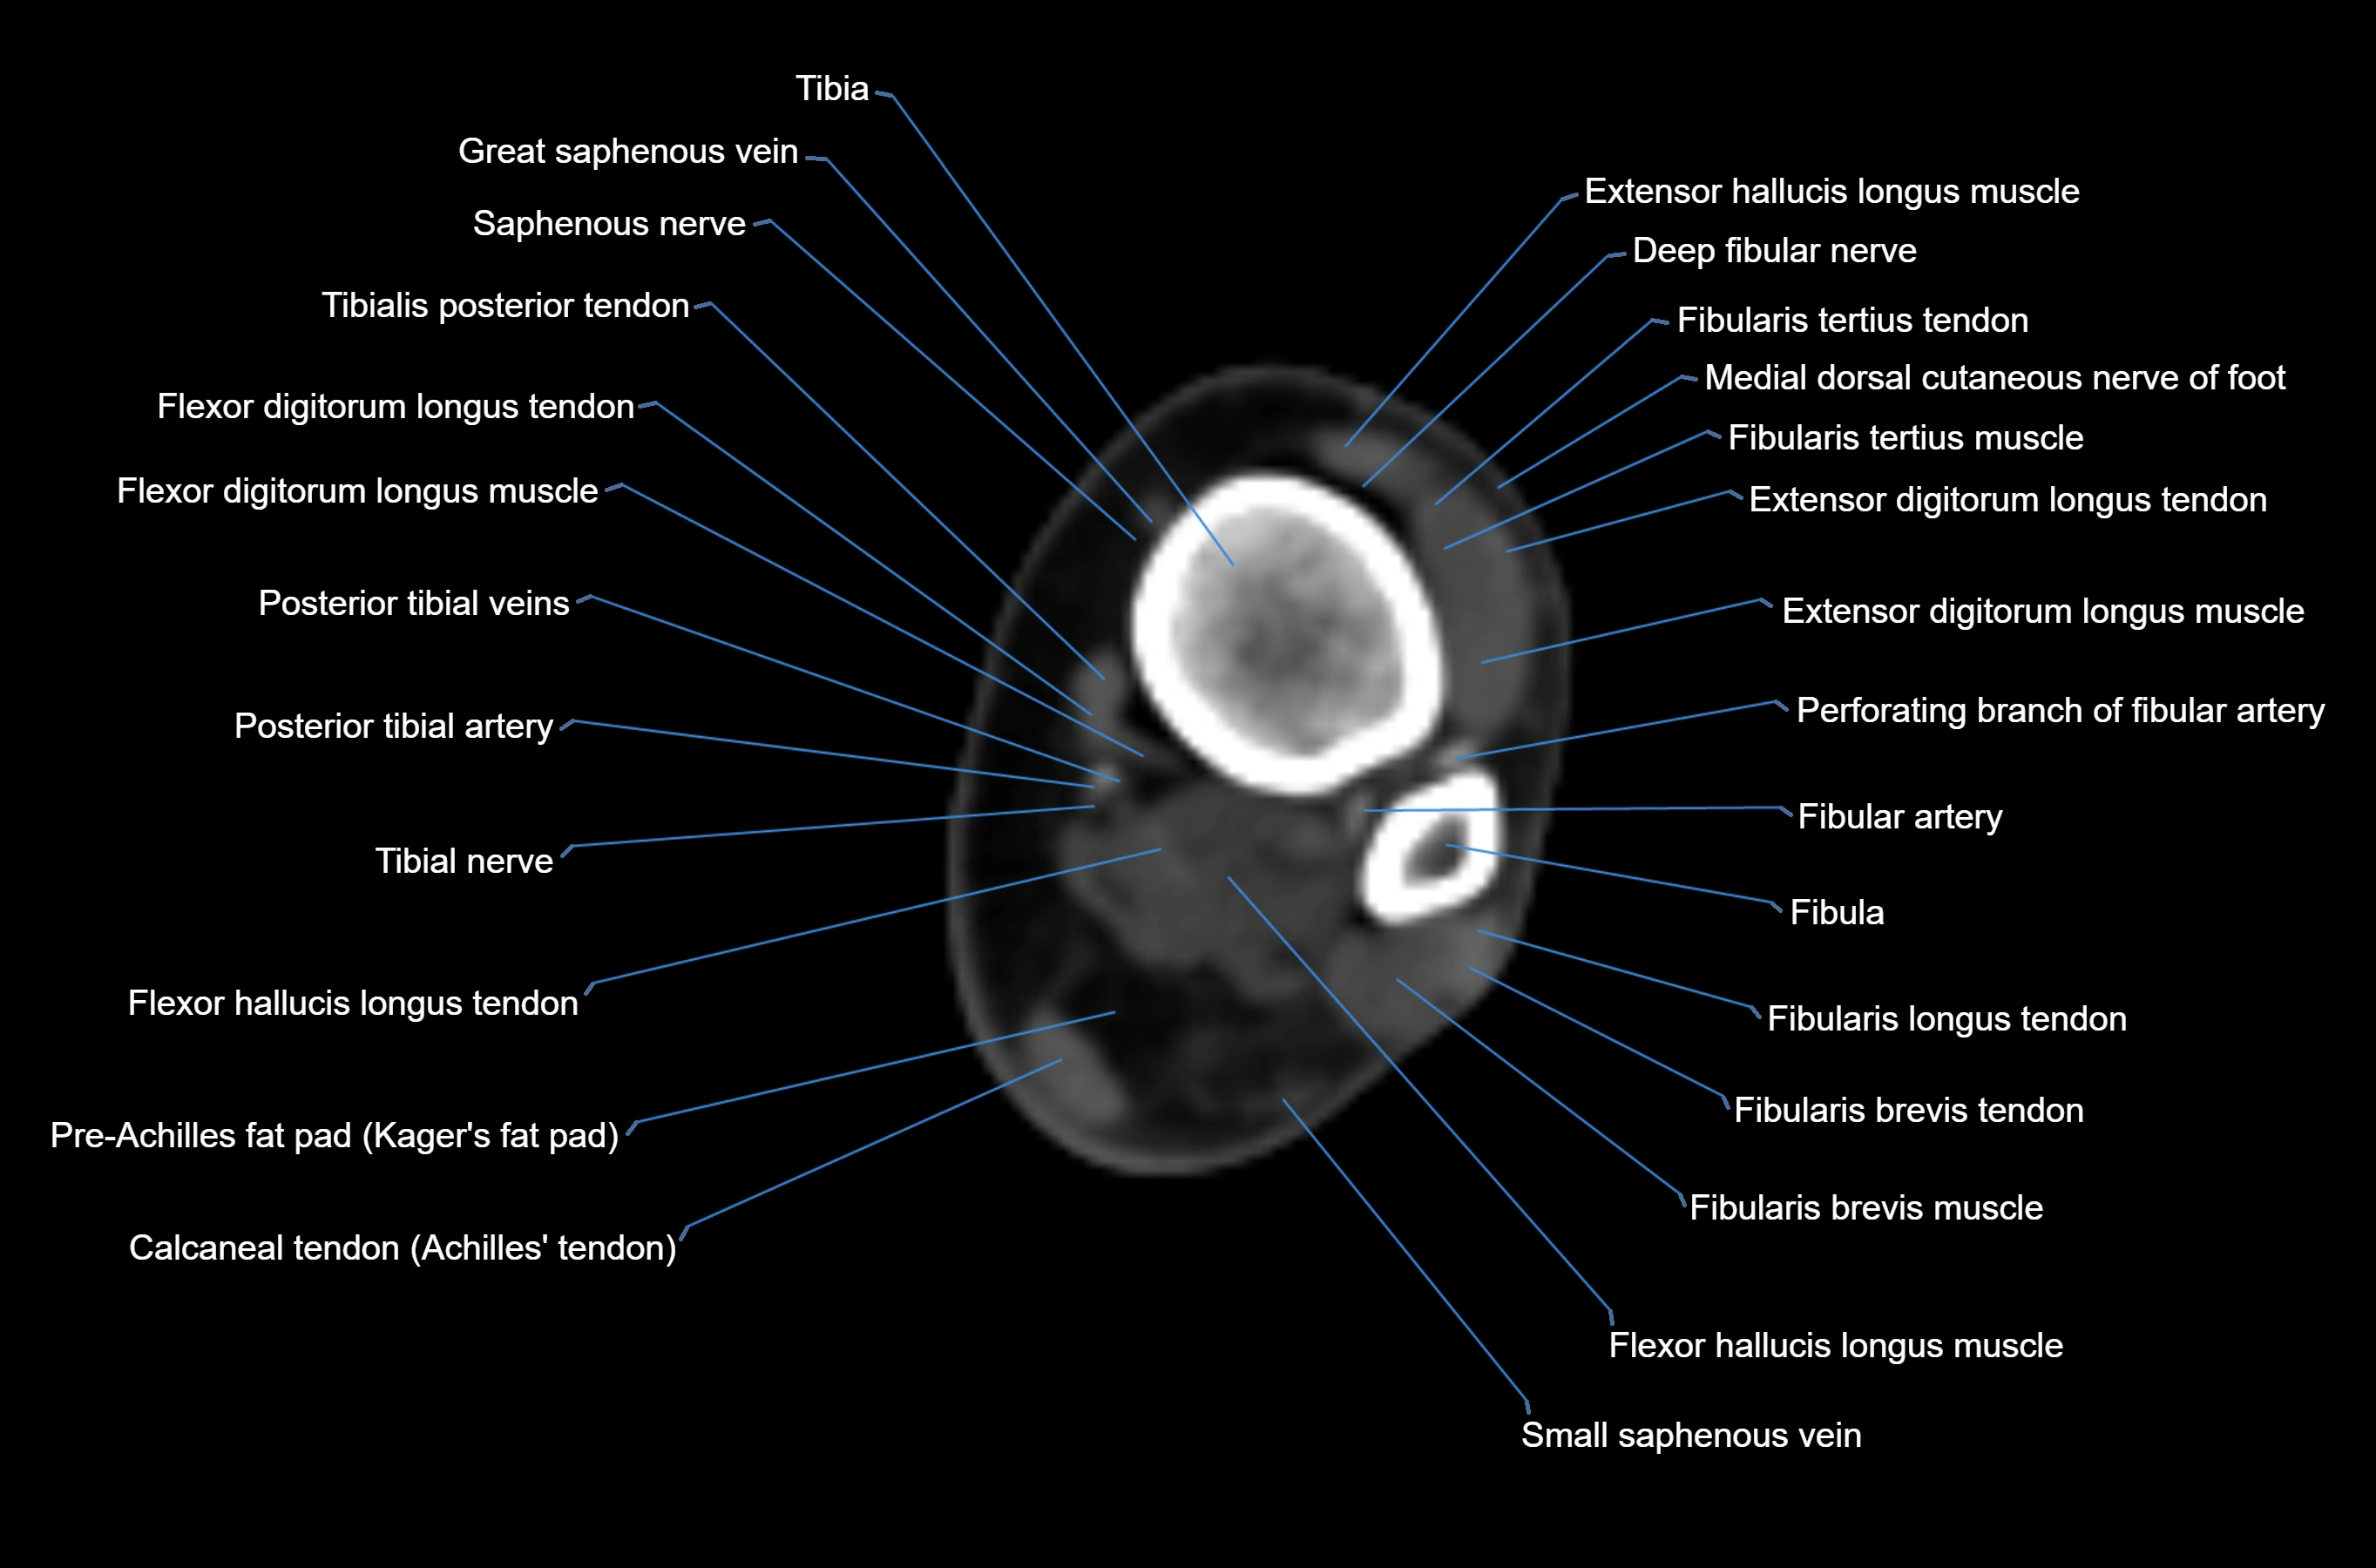

CT image